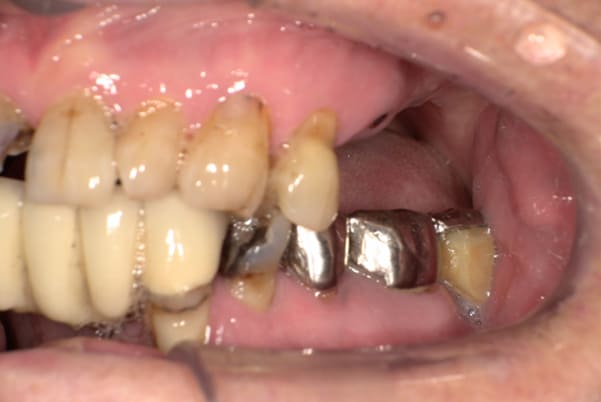

上前歯はブリッジの差し歯により根が折れ炎症を起こしお痛みのある状態でした。

原因は長期使用により下の義歯の歯が削れたことにより、下前歯が上前歯を突き上げ強い力が加わっていたことが根本的な原因と考えられます。

治療前は、奥歯が下がり、かみ合わせが乱れています。適切な入れ歯はそのままのかみ合わせで義歯を作るのではなく治療後のように、前歯から奥歯までのラインが真っすぐ揃った、かみ合わせの面を適切に付与し、よく咬め、残りの歯に負担がかからないかみ合わせとしました。

治療前の入れ歯の奥歯は、治療後の義歯と比較しても分かるように、歯が削れ平らになった状態です。

これにより奥歯のかみ合わせは低くなり、前歯のみが強くあたり、かみ合わせにより上の前歯大きな負担がかかっていたことにより、上の前歯が折れたことが考えられます。